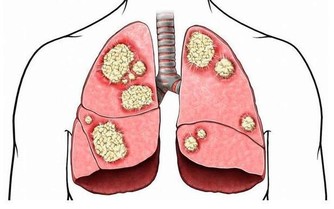

肺部

1.兩眉間發暗,為肺部久病。

2.右側臉頰特別是顴骨處發紅,為肺有熱病,但是在未發將發之時。

3.肺初病者,特別是初受風邪,在面部再現為兩眉上發白。

4.喘息鼻張者為肺病已久。